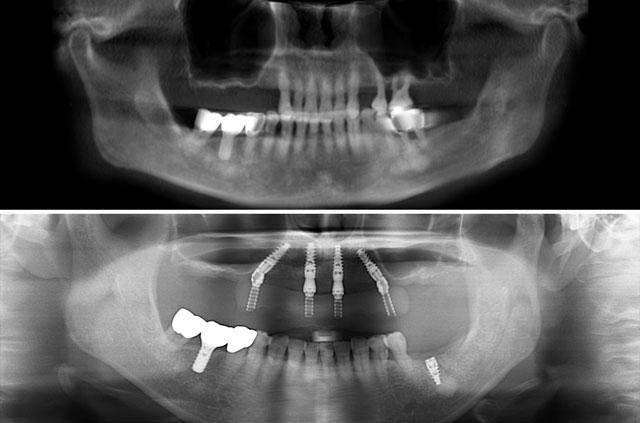

Real before-and-after results from single-tooth implants, All-on-4, All-on-6, and full-arch reconstruction cases.

Each case demonstrates the transformative power of dental implants, from single tooth replacement to full-arch restoration. Our All-on-4 Teeth-In-A-Day technique provides immediate results and long-term stability.

All-on-4 is a revolutionary dental implant technique that uses just four strategically placed implants to support a full arch of replacement teeth. The posterior implants are angled at 30-45 degrees to maximize bone contact and avoid anatomical structures like the maxillary sinus or inferior alveolar nerve. This innovative approach allows for immediate loading with a temporary prosthesis, providing same-day teeth and eliminating the need for lengthy healing periods between procedures.